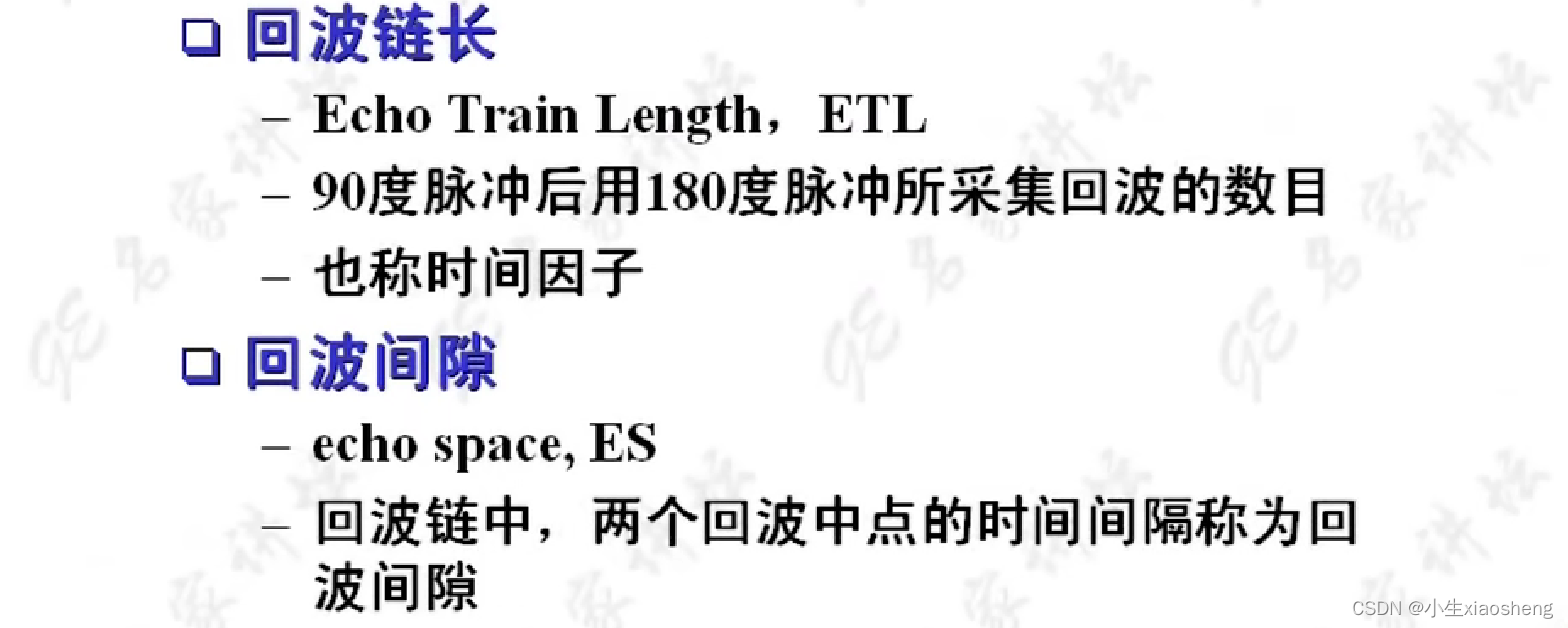

因为这里有很多的180度,所以一次能填充很多K空间线。两个90度之间的时间还是叫做TR,180度的个数叫做ETL,90度到中间个数的180度叫做有效TE,两个180度之间的叫做ES。